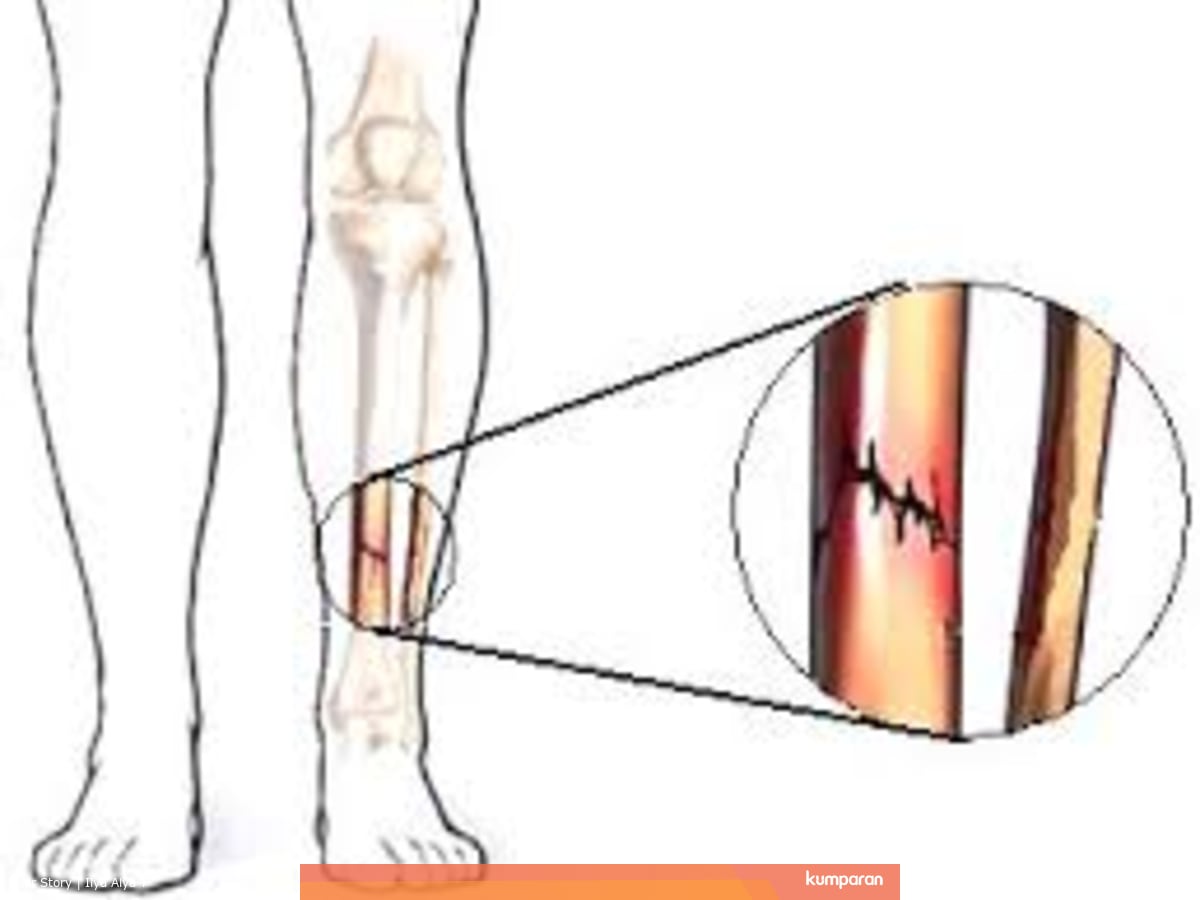

Mari Us Tahu Tentang Pengobatan Patah Tulang Tibia - Siiora.co.id

Mari Us Tahu Tentang Pengobatan Patah Tulang Tibia - Siiora.co.id

Berapa Lama Waktu Pemulihan Patah Tulang Kering? - Bolatory

Berapa Lama Waktu Pemulihan Patah Tulang Kering? - Bolatory